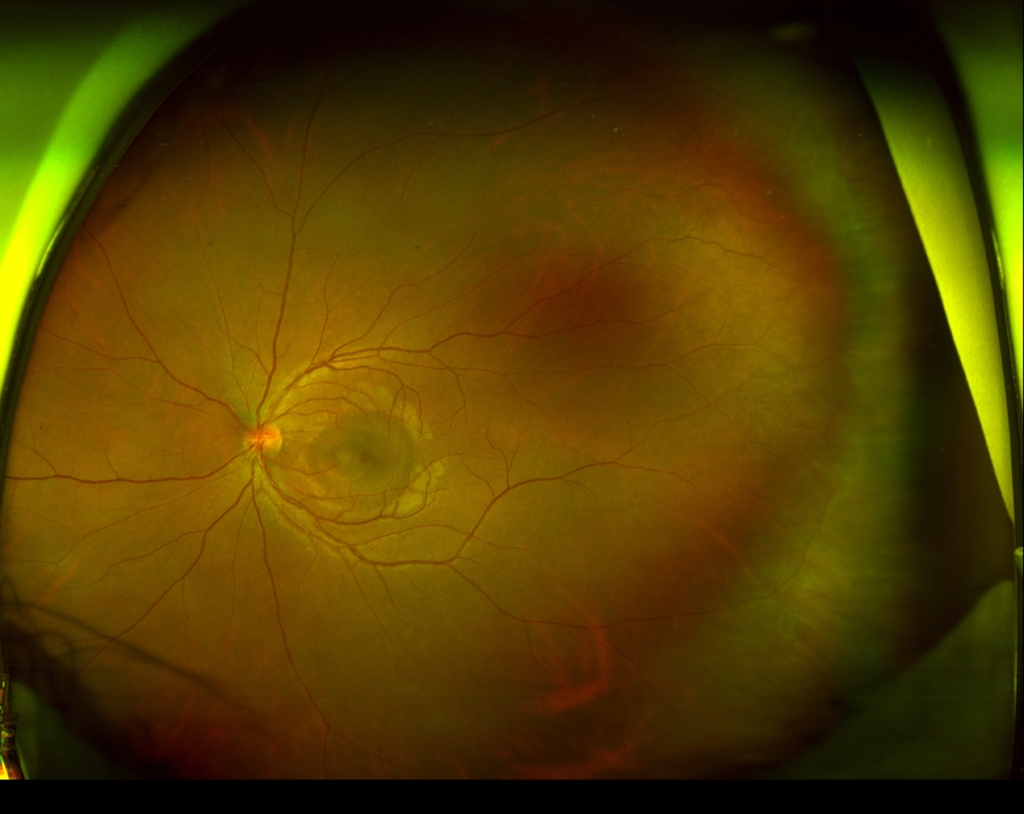

黄斑部に円形病巣がみられ、その鼻側縁に黄白色病巣がみられる。